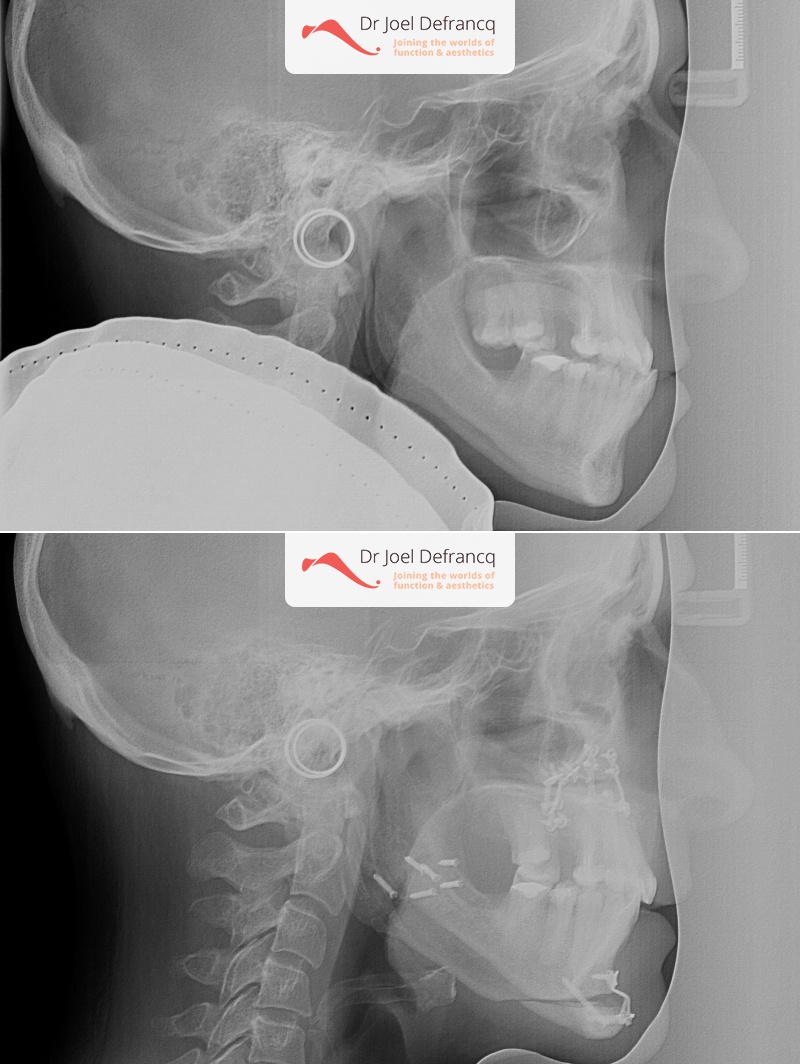

Kaakchirurgie

- Verlenging onderkaak (BSSO)

- Verlenging bovenkaak (Le Fort I)

- Rotatie bovenkaak

- Onderkaak rotatie

- Kinchirurgie